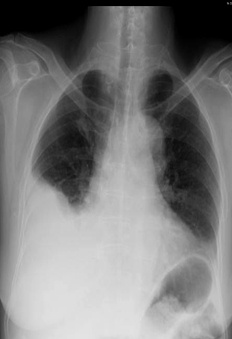

解題:片中可見肋膈角消失,根據(jù)公式得出胸腔積液